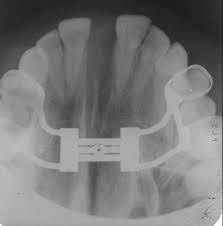

Hyrax aparelho preço. Dilatação total de 5 a 11mm Uma volta completa. Expansor p disjunção Palatina. Já para o fixo estético brackets transparentes o preço deve variar entre R 100000 a R 250000.

Disjuntor mais utilizado em disjunções rápidas da maxila. O HYRAX é um aparelho expansor preso aos dentes pela parte interna junto ao céu da boca. Quanto ao hyrax espero também não ter que ativa-lo mais.

OS PARAFUSOS HIRAX MORELLI ABREM 2MM A MENOS QUE O INDICADO NO PARAFUSO. Mousepad Hyrax 900x400 Bordas Costuradas Ilustrado Colorido. 79 reais con 28 centavos R 79.

Ele é usado em casos que o osso maxilar é muito estreito.